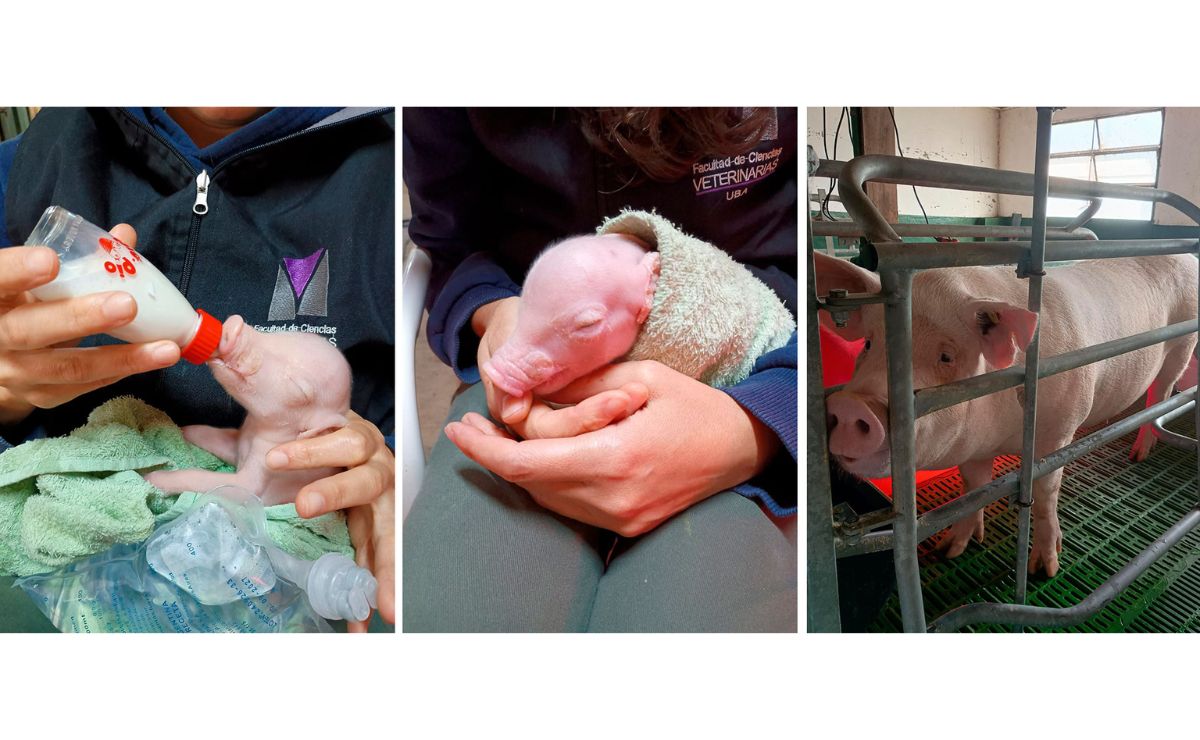

Nace el primer cerdo clonado para trasplantes de Latinoamérica

Científicos de Argentina lograron el nacimiento de un cerdo genéticamente modificado con vistas a que sus órganos puedan ser trasplantados a humanos.

Se trata del primer cerdo clonado de Latinoamérica y el tercer caso documentado del mundo, después de Estados Unidos y China.

El avance es fruto de un consorcio científico conformado por la Facultad de Ciencias Veterinarias de la Universidad de Buenos Aires (UBA) y del Instituto de Investigaciones Biotecnológicas de la Universidad Nacional de San Martín (UNSAM) de Argentina.

Según destacó la UBA en un comunicado, se trata de un “hito histórico” al gestar un clon porcino con tres modificaciones genéticas adaptadas para burlar las defensas humanas, un paso crucial para el trasplante de órganos.

La etapa de clonación molecular y edición de los embriones se llevó adelante en laboratorios de la UNSAM.

Allí los científicos lograron un clon generado a partir de células modificadas en las que desactivaron los tres genes responsables de desencadenar la respuesta inmune agresiva que termina destruyendo al órgano cuando es rechazado al ser trasplantado a un cuerpo humano.

El equipo de la Facultad de Veterinaria de la UBA se encargó de llevar a ese clon desde la inseminación hasta el nacimiento en abril pasado de un primer lechón.

“Somos los responsables del mantenimiento de la gestación y el parto, es decir, somos el eslabón final del proyecto, pero también el inicio de la etapa de crianza de los lechones”, contó el veterinario Marcelo Acerbo, profesor de la Facultad de Veterinaria de la UBA.

Los expertos ya tienen dos cerdas preñadas más a su cuidado y su plan es contar con cinco clones más.

El paso siguiente del proyecto será sumar siete genes para hacer que el órgano del cerdo sea más compatible con el organismo humano receptor.

“Esto incluirá el bloqueo de hormonas de crecimiento para moldear y adaptar el tamaño del hígado o el corazón porcino, que en animales adultos de más de 200 kilos excede la capacidad del cuerpo humano, asegurando que los órganos sean completamente funcionales”, explicó Acerbo.